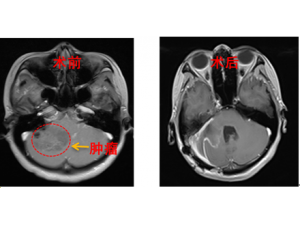

孕妇颅内长巨大肿瘤 军医紧急剖宫产后再切肿瘤 孕妇颅内长巨大肿瘤 军医紧急剖宫产后再切肿瘤 … [详情] -